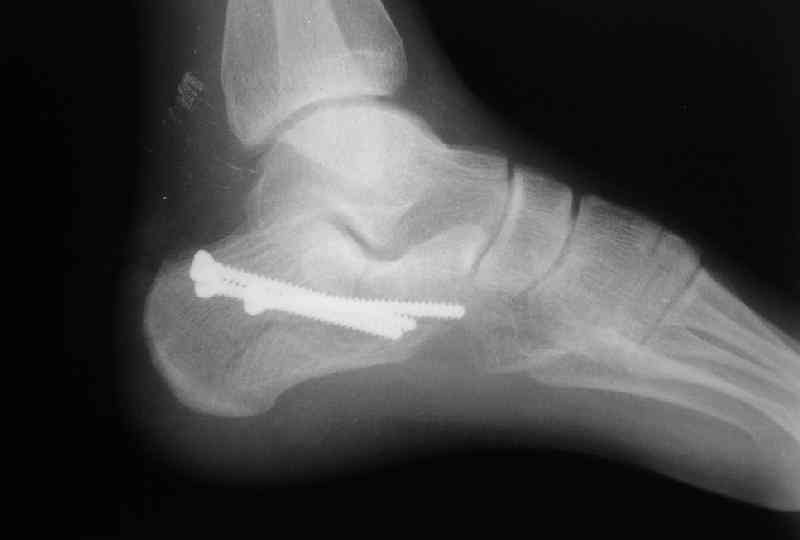

Re: Перелом пяточной кости

Пяточной пластиной

Открытый и закрытый способы лечения.